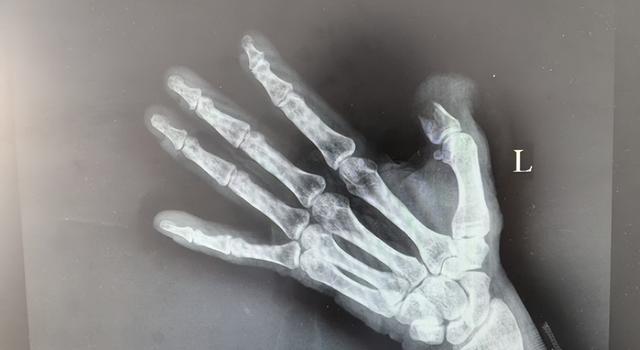

2025年1月10日,宁远县一名40岁的泥瓦工人黄大哥,在工作时发生意外,导致左手拇指被严重碾压性损伤。他立刻赶往当地医院就诊。然而,初步检查结果并不乐观,医生告知他只能进行拇指残端修整。

抵达郴州市后,黄大哥在手足显微外科接受了详细的检查。医生们发现,其整个拇指前端已经全部被切割掉,为了保留拇指功能,提议他进行“足趾代手指再造”术。该手术方案需要取患者的脚趾,移植到拇指的位置,以替代受损的拇指。

1月14日,经过充分的术前准备,手足显微外科团队开始实施这场对黄大哥来说意义特殊的手术。手术由副主任医师刘小仁与主治医师陈耀武、曹焱鹏联合主刀,考虑到黄大哥的职业特点和实际需求,医生们决定使用右足的第二个脚趾进行移植,因该脚趾不仅功能适宜,而且外观相对美观。整场手术持续了近4小时,在医生们的精湛技艺与通力合作下,黄大哥右脚的脚趾成功移植到了左手残缺的拇指位置。